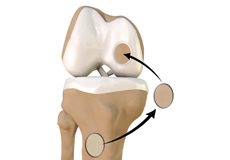

Loose Bodies in the Knee

Loose bodies are fragments of detached cartilage or bone inside the knee joint. These fragments may be free floating (unstable) or may be trapped (stable) within the joint.